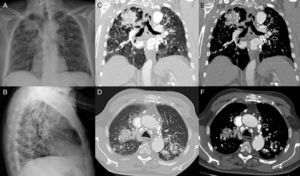

La radiografía de tórax mostraba un patrón nodular bilateral difuso con opacidades posteriores en lóbulos superiores, asociadas a pérdida de volumen, retracción hiliar y enfisema compensador de los lóbulos inferiores. Así mismo se observaron adenopatías hiliares bilaterales con calcificaciones periféricas en «cáscara de huevo» (fig. 1A,B,E,F).

Radiografía posteroanterior (A) y lateral de tórax (B): opacidades bilaterales en lóbulos superiores de localización posterior (visibles en B), asociadas a pérdida de volumen, retracción hiliar y enfisema compensador de los lóbulos inferiores. Patrón nodular bilateral difuso. Adenopatías hiliares con calcificaciones periféricas en «cáscara de huevo». TC. Imágenes coronales (C, E) y axiales (D, F) en ventana de pulmón y mediastino, respectivamente: opacidades bilaterales en segmentos posteriores de lóbulos superiores con calcificaciones puntiformes en su interior. Enfisema paracicatricial entre la opacidad del lóbulo superior derecho y la pleura adyacente (asterisco). Múltiples nódulos centrolobulillares de distribución bilateral y difusa. Adenopatías mediastínicas e hiliares con calcificaciones en «cáscara de huevo» (flechas).

La TC demostró la presencia de calcificaciones puntiformes en el interior de las opacidades y la existencia de un enfisema paracicatricial entre la opacidad del lóbulo superior derecho y la pleura adyacente (fig. 1C,D).